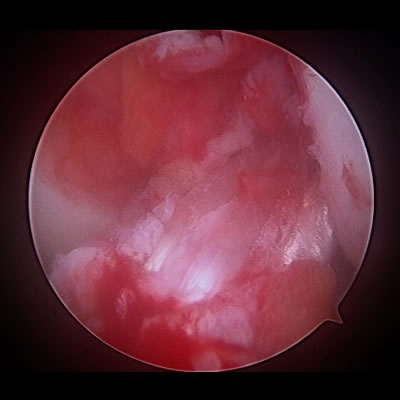

関節鼠摘出術(外側型野球肘(離断性骨軟骨炎・関節内遊離体))

関節鏡で肘関節の中を確認し、細い処置具を使って、引っかかりや曲げ伸ばしの制限の原因になっている遊離体(関節ねずみ)を摘出し、傷んでしまった軟骨をクリーニングします。